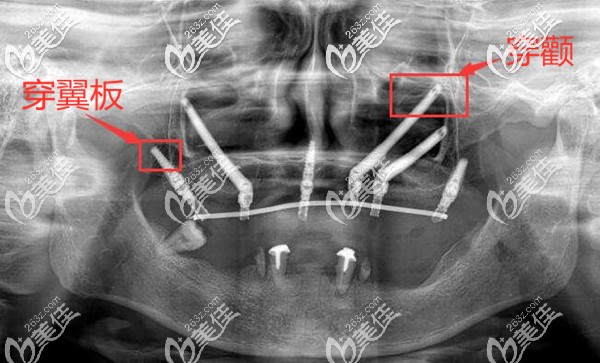

簡單的來說,穿顴穿翼板種植牙技術,是專門解決上半口牙齒缺失牙槽骨又萎縮比較重的種牙問題;也是一種高難度種植牙技術。

穿顴穿翼板種植,主要是用比傳統(tǒng)種植體多出3-4倍長度的種植體,植入到顴骨和翼板骨部位。

穿顴穿翼板種植牙可謂是種植界頂峰的技術,對醫(yī)生的技術要求非常高;所以種植前醫(yī)生通過各種檢查,詳細了解種植區(qū)域鄰近的動脈、靜脈和神經(jīng)的位置,只有這樣才能夠避免手術的風險,以及術后的并發(fā)癥,如出血、損傷面部和眼部神經(jīng)等。

不過,也不用過于擔心,因為現(xiàn)在能做穿顴穿翼板種植的醫(yī)院,都會現(xiàn)在3D打印來出來的頜骨模型模擬手術,真正的手術中還配備有3D導板,手術中的定位也會更精準。